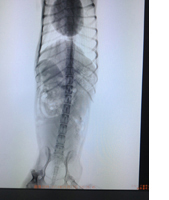

先月のこと散歩途中にいつもの通りボール遊びをしていました。ボールを投げては咥えて走って戻ってきます。何度か繰り返していた次の瞬間、走っている途中に『キャン!』という声とともに腰が落ち、後の脚が伸びて動かせない彼女の姿がありました。一瞬、何が起きたのか判らず彼女のもとに走って行くと、とてもつらそうな声で鳴きながら、上手く使えない体を必死に動かそうとしていました。私自身、股関節を脱臼したのか?骨折したのか?初めてのことで彼女を見る限りでは全く判りません。直ぐに病院に連れていき診察を受けました。診断は腰椎の椎間板ヘルニア。

椎間板は脊椎骨と脊椎骨の間に位置して、背骨にかかる衝撃を吸収してくれる役割をしています。中身はゼリー状の衝撃吸収素材で、椎間板があるおかげで勢いよく走ったり身体をひねったりしても背骨が柔軟に動きダメージを緩和してくれるわけです。この椎間板が正常な位置から飛び出してしまい、神経を圧迫することにより痛みと下肢の麻痺がおこります。人間にも椎間板ヘルニアは発症する傷害です。(私自身も診断を受けました)

人の手によって品種改良されたダックスフンドやフレンチブルドックなどは軟骨異栄養性犬種と言われ軟骨の変性が起こりやすい体質を持つようです。背骨には日常生活でもかなりの力が加わっています。特にダックスのような胴長の犬種はそのリスクが高くなります。

うちの子はダックスフンドで、やはりヘルニアを起こすリスクは高い犬種です。診断を受けた後は、治療に入ります。 10日ほど入院して安静を維持し、電気鍼、温泉治療など人とほぼ同じ治療をしていました。 戻っては来た時は痛みは回復しているようで、一生懸命歩こうとしていますが、腰から下の筋肉が麻痺により低下して腰が落ちたままの状態でほぼ脚では立つことはできません。 関節も曲げ伸ばしが上手くできないので、マッサージをしたり曲げ伸ばしの手伝いをしたり、積極的に動かすようにしました。